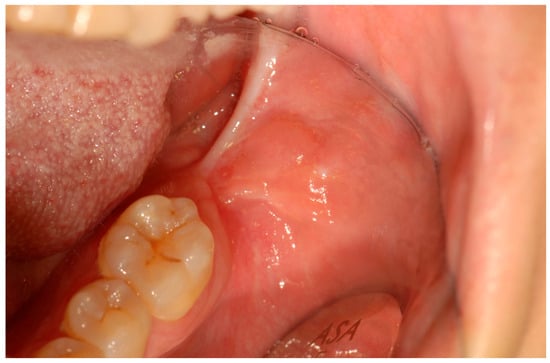

A 39-year-old Caucasian woman was referred by her dentist to the Department of Oral Sciences and Maxillofacial Surgery, Polyclinic Umberto I, “Sapienza” University of Rome, for evaluation of multiple exophytic and erythematous lesions in the left retromolar region (Figure 1). The lesions had been present for approximately five months and were associated with occasional minor bleeding following local trauma. The patient also reported mild pain and a recent increase in the size of the lesions during the two weeks preceding the visit. Her medical history included systemic lupus erythematosus (SLE), diagnosed in 2000 at the Department of Clinical Medicine, “Sapienza” University of Rome, following symptoms of gastroesophageal reflux, low-grade fever, diffuse arthromyalgia, a previous pericardial effusion, and positivity for ANA and ENA SS-A antibodies. She was under treatment with prednisone and cyclophosphamide, levothyroxine sodium for hypothyroidism, and omeprazole for gastroesophageal reflux. The patient was allergic to penicillins and denied regular tobacco or alcohol use. In 2015, she developed ocular vasculitis with photosensitivity, prompting replacement of cyclosporine with cyclophosphamide.

Figure 1.

Erythematous and exophytic lesion located on the left retromolar trigone. The blue arrow indicates the lesion located at the retromolar trigone.